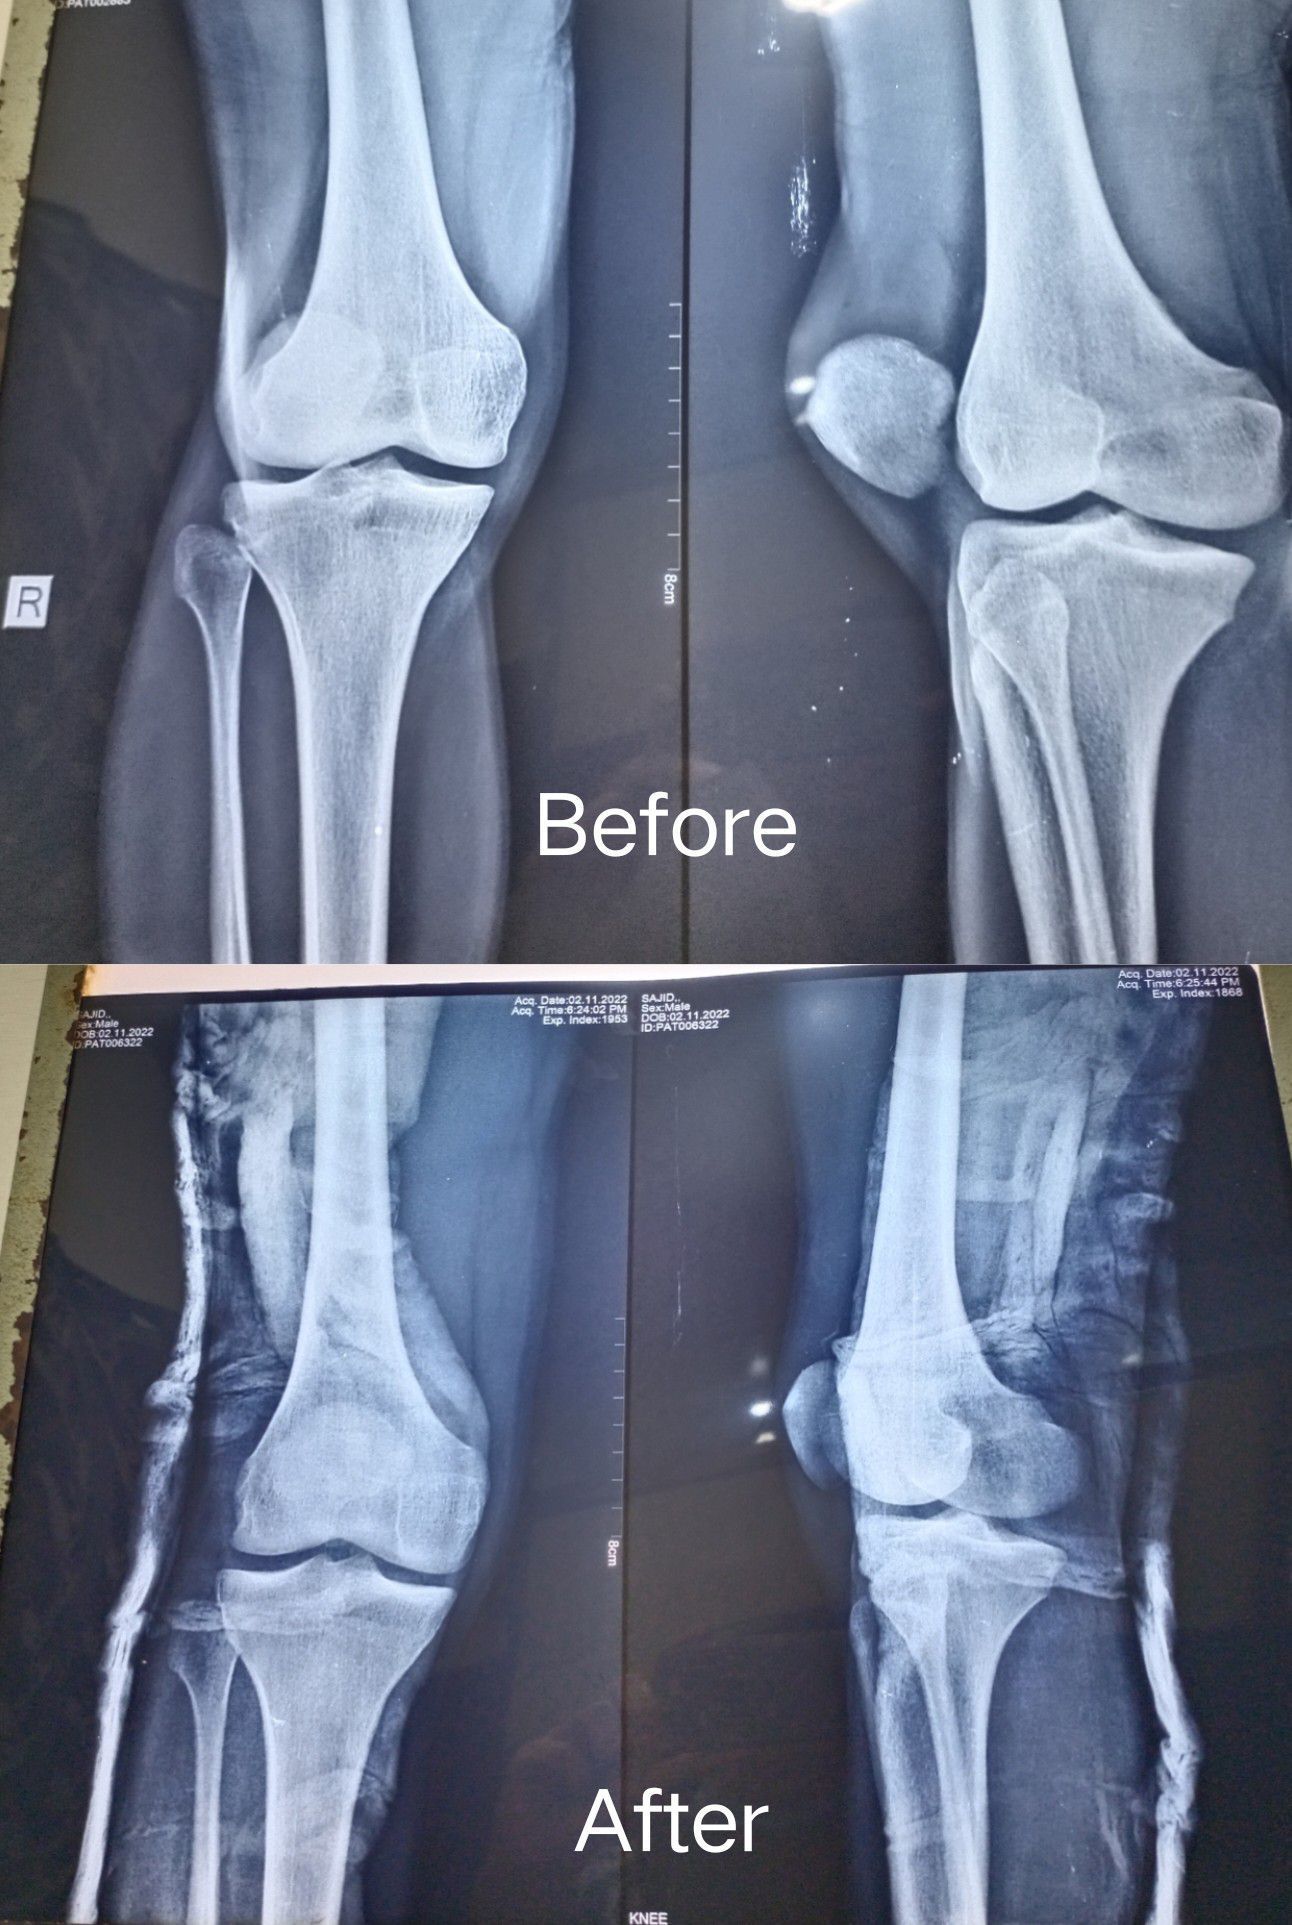

Patellar dislocation

Patella